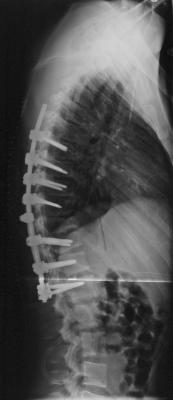

Der Körper versucht immer den Kopf gerade über dem Becken zu halten.

die Lordose entsteht nur, damit der Pat. geradeaus sehen kann und verschwindet sofort wieder, wenn man die Ursache (die BWS Kyphose) wegnimmt.

Das gelingt umso besser, je flexibler die Wirbelsäule noch ist.

Bei einer Skoliose kann man mit 15 die VErsteifungsstrecke auch sehr viel kleiner halten als mit 35 oder 30, weil man in der REgel nur eine und nicht zwei Krümmungen operativ begradigen muß. (anbei zwei Bilder)

Muskulatur und Bander passen sich sehr schnell an. eine solche geringere Lordose braucht ja eher weniger Muskelarbeit, daher werden ja auch die Schmerzen, die durch die Überlastung der Muskulatur bei einer Hyperlordose verursacht sind weniger.

- Auch hier wurde nur die strukturelle Hauptkrümmung der BWS korigiert und ich glaube, dass ich dadurch die Beweglichkeit der LWS auf Dauer verbessert habe.

- Skoliose_post.jpg (9.72 KiB) 22637 mal betrachtet

- Skoliose_prä.jpg (12.36 KiB) 22637 mal betrachtet